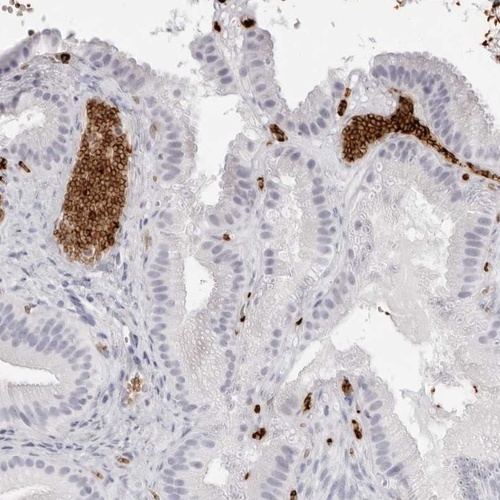

Immunohistochemical staining of human gall bladder shows strong cytoplasmic positivity in red blood cells.